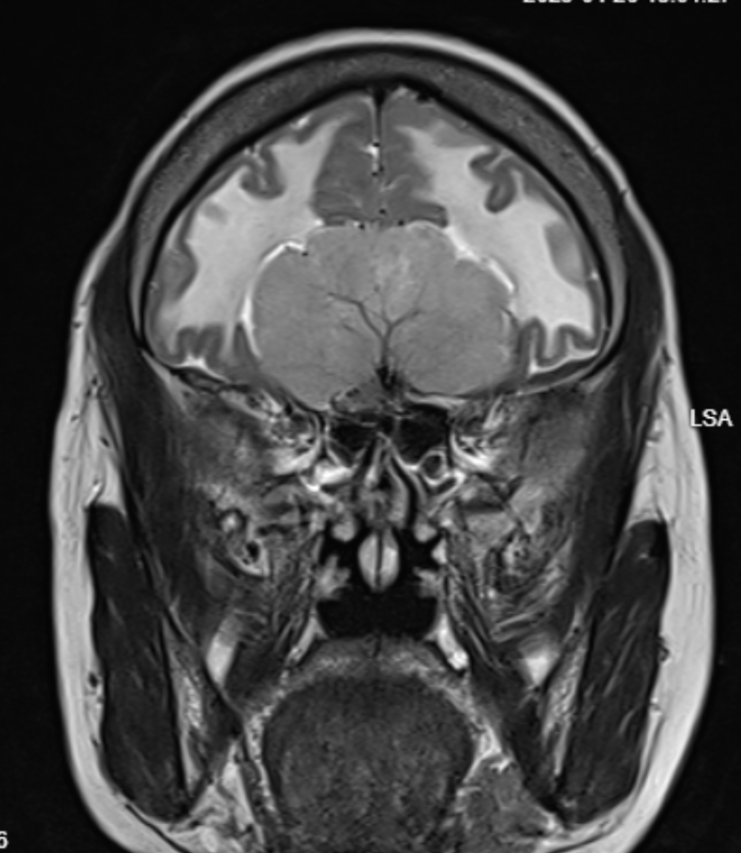

MRI Scan Analysis CT Scan Analysis Temporal Scan Analysis Orbits Scan Analysis MRI Scan Analysis CT Scan Analysis Temporal Scan Analysis Orbits Scan Analysis

Primary Reads & Second Opinions

We do primary reads and second opinions. For collaborating or partnering for primary reads of scans, please connect with us at reach@hnnradiologist.com.

MRI Brain / Spine: ₹1000